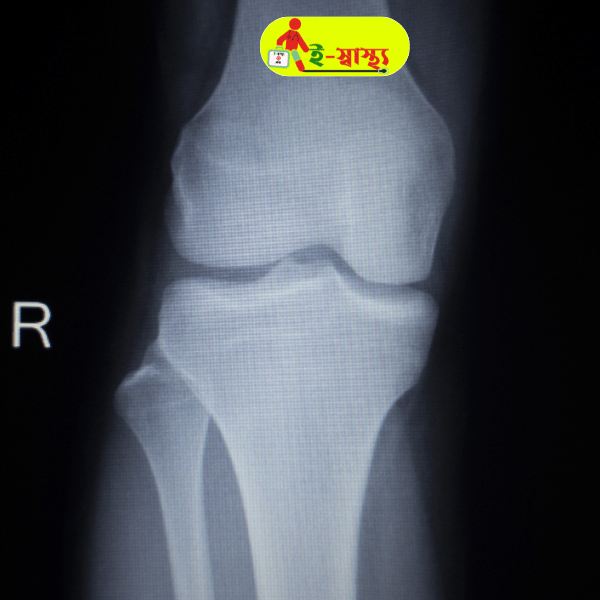

X-Ray for knee joints is an imaging technique to assess the knee joint for alignment, bone quality and the extent of a degenerative changes within the knee. It is advised by the doctor to detect any fracture, injury and osteoarthiritis. Common symptoms of an knee disorder include pain, tenderness, swelling and deformity of the knee.

X-Ray for both knees, also known as bilateral x-ray is recommended if a physician suspects the symptoms of arthiritis.